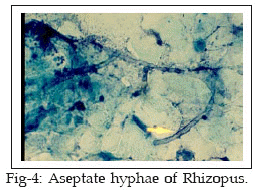

Fifteen patients attending at the Jahad and Razi Laboratories supposed to be suffering from disease were involved in this investigation. It included 11 female (73.3%) and 4 males (26.7%). The ages of the patients ranged between 4-30 years with a mean of 17 years. All patients had one or more of the aural symptoms (itching, otalgia, hearing loss). Secretion and pus were collected from the ear by two sterile cotton wool swabs. One swab was used for direct microscopy and other for culture examination. Direct examination of the samples was carried out by staining the smears with methylene blue and Gram techniques. Otomycosis was confirmed by the presence of aseptate mycelium, septate mycelium, Aspergillus conidia, fruiting bodies, yeast and pseudohyphae (Figs 1-4). The presence of fungal elements in stained smears was re-confirmed by fungal culture fungal colonies. Any kind of clinical materials, especially liquid samples (swabs, pus) should be examined as quickly as possible. Swabs did not require processing and were directly used for culture. Swabs were rolled and inoculated over the surface of Sabouraud’s Dextrose Agar with chloramphenicol (SC). Cultures were incubated at laboratory ambient (25-27°C) for 2-3 weeks, aerobically. Fungal isolates (moulds) were identified on the basis of colonial morphology and slide cultures. Yeast colonies, also detected by germ tube test, production of chlamydoconidia on corn meal agar and API 20 C AUX system.

Results